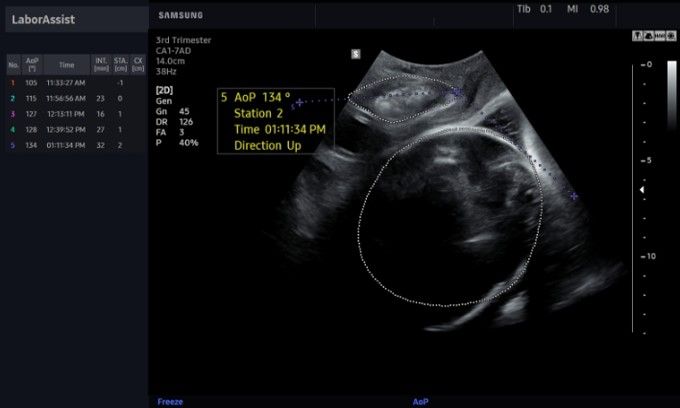

This clearance applies to lung and cardiac imaging in patients with viral infection.

Onvision is designed to increase accuracy of needle placement during peripheral nerve blocks.